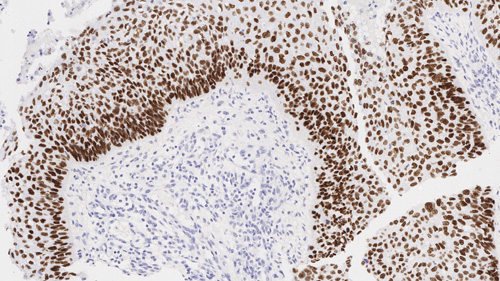

Immunohistochemical staining for Helicobacter pylori: clone ULC3R

Helicobacter pylori is recommended for the detection of specific antigens of interest in normal and neoplastic tissues, as an adjunct to conventional histopathology using non-immunologic histochemical stains.